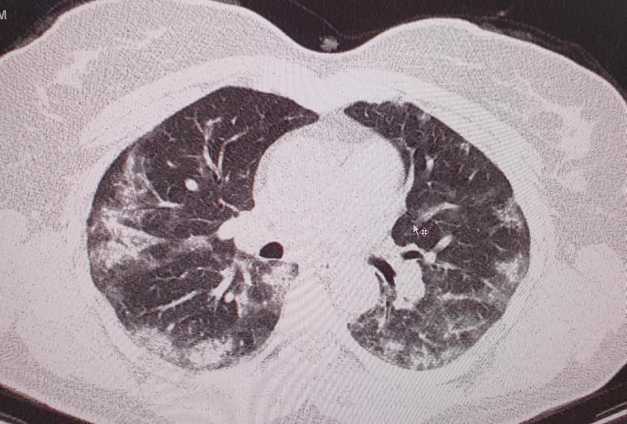

Pentru a demosntra existența formelor atipice ale bolii Covid-19, medicul din Craiova a făcut publice două imagini cu plănânii unei femei infectate cu noul coronavirus, care nu prezenta comorbidități.

„Forme atipice de Covid-19. Toţi medicii care se confruntă cu patologia Covid-19 ar trebui să se gândească la această boală şi în cazul unui pacient cu simptome ,,ciudate” apărute în plină stare de sănătate! Unii mă vor întreba ce înţeleg prin simptome ciudate! Medicii înteleg ce spun! Astăzi am depistat un caz de Covid 19 la o pacientă relativ tânără, fără febră, fără tuse..fără niciun simptom considerat tipic sau sugestiv pentru Covid-19! Faptul ca am folosit ecografia pulmonară ce mi-a relevat modificări sugestive, m-a convins de necesitatea unui examen CT pulmonar. Examinarea tomografică a fost concludentă. Ulterior, a urmat şi confirmarea serologică. Simptomele pacientei erau doar astenie marcată, ameţeli, somnolenţă. Saturaţia in oxigen 98%! Fără comorbidităţi!”, a scris medicul craiovean.

Publicând cele două imagini, medicul a arătat ce modificări au suferit plămânii pacientei confirmate cu SARS-CoV-2. Fiecare fotografie a fost însoţită de explicaţii.